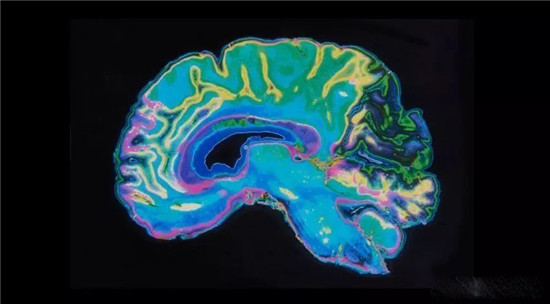

加州大学旧金山分校的一项研究发现,两种对阿尔茨海默症病理学起重要作用的蛋白质(淀粉样蛋白β(Aβ)和tau蛋白)起着朊蛋白的作用,而这种畸形的蛋白通过「迫使」正常蛋白质采用与其相同形式的错误折叠,导致其在大脑组织中传播。

目前阿尔茨海默病的定义是,基于存在于大脑中的被称为淀粉样蛋白斑块和有毒蛋白质聚集为病理基础的、同时伴有认知功能衰退和痴呆症状的神经系统退行性疾病。